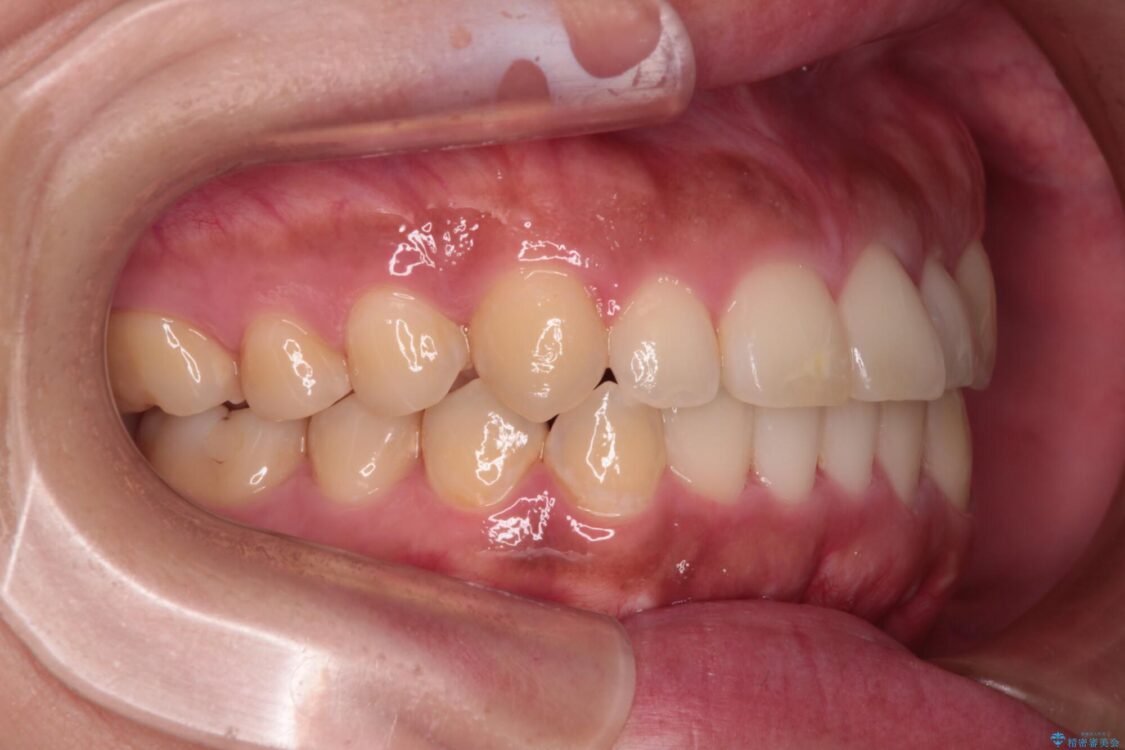

治療途中

• 【モニター】カリエール・ディスタライザーを併用した八重歯のインビザライン矯正 治療途中画像